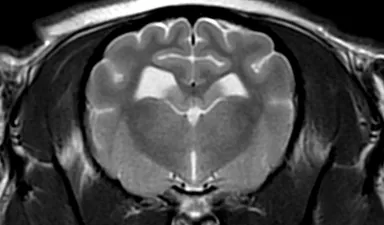

■MRI検査

強力な磁石と電波を用いて体内の水・脂肪成分の情報を収集し、断層像を得る検査です。軟部組織のコントラストが非常に優れているため、特に脳や脊髄といった中枢神経系の検査に威力を発揮します。

MRI検査画像

GE社製 1.5T MRI装置 SIGNA Explorer